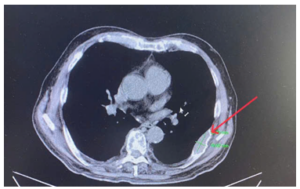

Ca lâm sàng: Điều trị bệnh nhân ung thư phổi di căn màng phổi, màng tim tại Trung tâm Y học hạt nhân và Ung bướu, Bệnh viện Bạch Mai

Ca lâm sàng: Điều trị bệnh nhân ung thư phổi di căn màng phổi, màng tim tại Trung tâm Y học hạt nhân và Ung bướu, Bệnh viện Bạch Mai GS.TS. Mai Trọng Khoa, PGS.TS.Phạm Cẩm Phương, BS CKII Võ Thị Huyền Trang, BS. Vũ Thị Huyền Ung thư phổi...